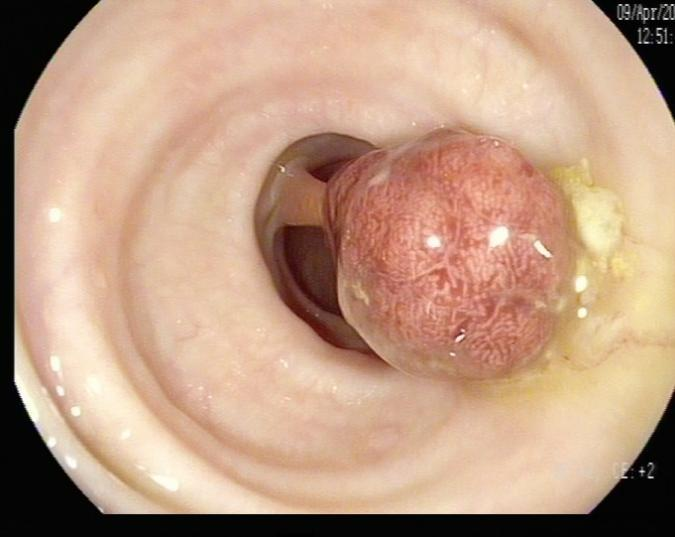

(4)黄先生(32岁,升结肠息肉,图4)

肠镜一照,息肉现形!形态各异的大肠息肉,离癌有多远?(图4)

图4

病理诊断:潴留性息肉(或称幼年性息肉)。

解读:这类息肉常见于儿童和青少年,但成人也可发生。是黏膜腺体扩张、分泌物潴留形成的错构瘤性病变,本质上是良性,通常不具有癌变潜能。距离癌:基本安全,良性息肉。